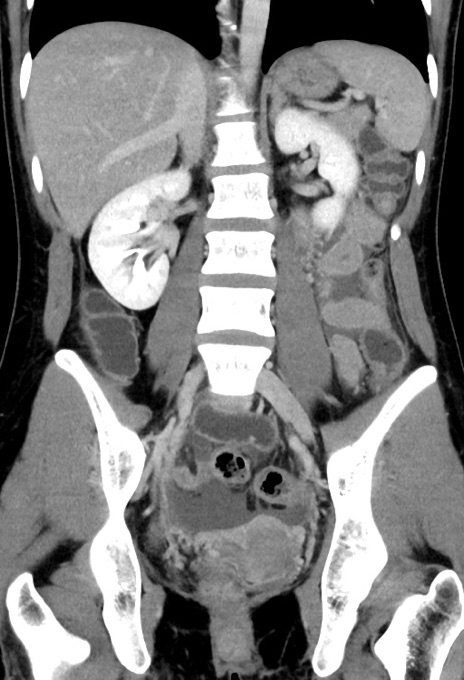

横断像

【症例】20歳代女性

【主訴】嘔吐、下腹部痛

【現病歴】昨日夕食後に嘔吐し下腹部痛が出現。本日になっても嘔吐持続し改善しないため来院。

【身体所見】意識清明、BT 37.2℃、BP 108/67mmHg、腹部:平坦、やや硬、下腹部正中から右にかけて圧痛あり、反跳痛軽度あり、tapping pain(+)。

【データ】WBC 13600、CRP 14.94